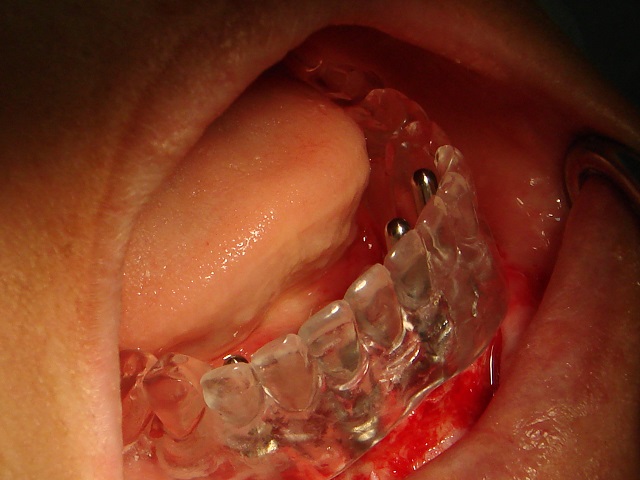

Entre a fase da instalação do implante e da confecção da prótese definitiva, o paciente usará uma prótese provisória para a manutenção do espaço e restauração estética, porém, através de novas técnicas e materiais disponíveis é possível a instalação da prótese definitiva sobre o implante em até 48 horas ou até mesmo no mesmo dia. Esta técnica é chamada de carga imediata.